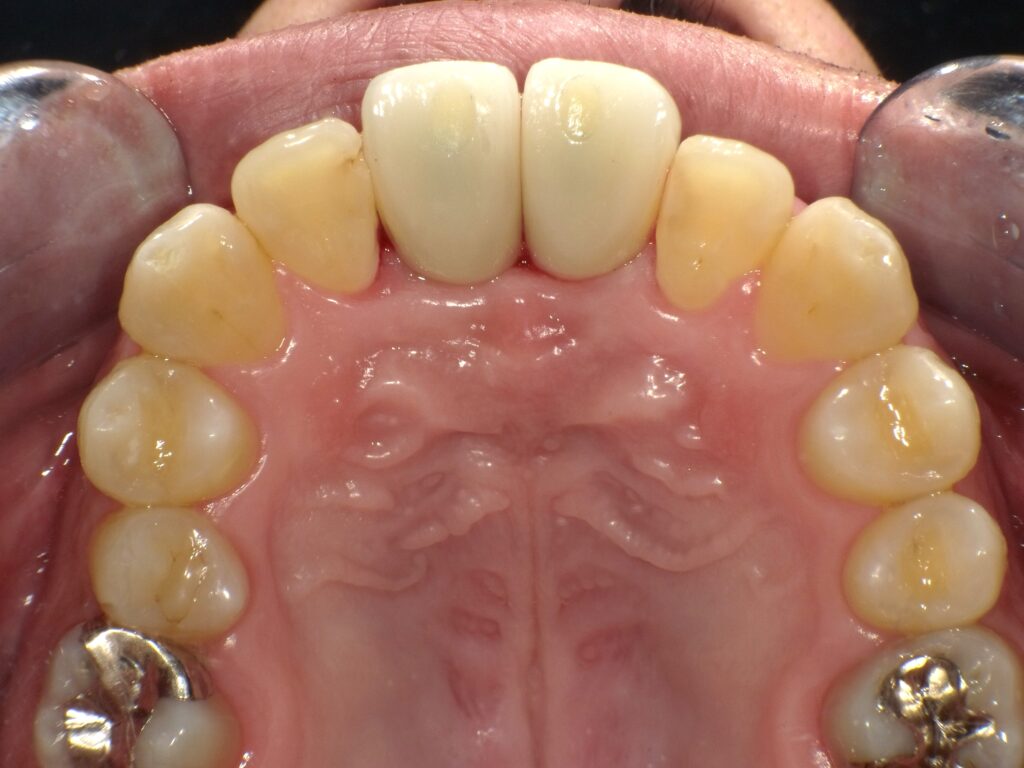

症例一覧 インプラント症例3 2024.11.25 治療内容インプラント主訴前歯部折れたのでインプラント治療を行いたい費用¥1259,500(2本)治療期間治療期間 7ヶ月 インビザライン症例1 前の記事 インプラント症例2 次の記事